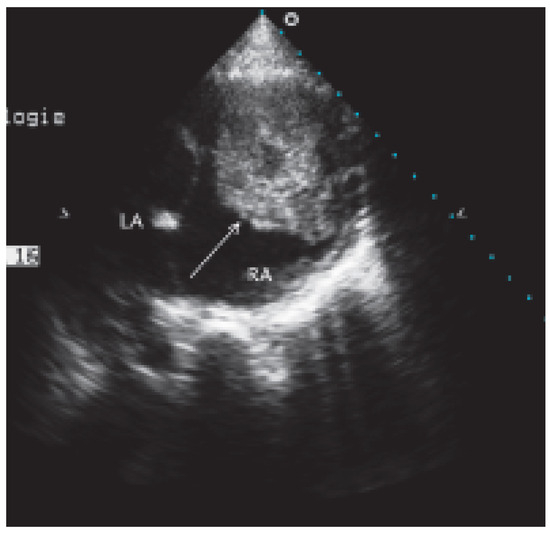

Valve Prosthesis in the Tricuspid Position: An Useasy Relationship

by P. Trigo Trindade, J. Sierra and C. Vuille

Cardiovasc. Med. 2006, 9(4), 167; https://doi.org/10.4414/cvm.2006.01163 - 28 Apr 2006

Case report. A27-year-old woman from Madagascar was referred to our institution because of right heart failure [...] Full article